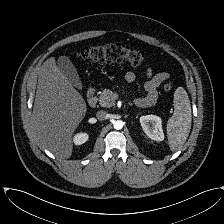

Multi-organ segmentation in CT images: The Synapse multi-organ segmentation dataset [70] contains 30 abdominal CT scans, where 18 (resp. 12) cases are used for training (resp. testing). The goal is to segment 8 abdominal organs. We also conduct evaluations on the AbdomenCT-1K dataset [71] containing more 1000 CT scans from 12 medical centers to benchmark the generalization ability of different methods.

Multi-organ segmentation: For multi-organ segmentation in CT images, Some illustrative results are shown in Fig. 4. Qualitatively, SIKD built on TransUNet [21] accurately segments different organs and preserves their shapes well. The quantitative benchmark on the Synapse multi-organ segmentation dataset is depicted in Tab. 2.

SIKD performs better than the corresponding baseline in terms of both Dice score and HD, implying that SIKD achieves good surface prediction and preserves the shapes better. Specifically, SIKD outperforms the baseline TransUNet by 2.69% Dice score and 8.04 mm HD. Compared with SwinUnet [23], SIKD based on TransUNet achieves an improvement of 1.01% Dice score and 1.89 mm HD. Implementing SIKD with MaxStyle [85] and SAMed [86] also consistently boosts the intra-dataset segmentation performance. The latest 2D D-LKA achieved state-of-the-art (SOTA) performance. Based on this approach, our method improves the Dice score by more than 1%.

We also benchmark the generalization ability of different methods by conducting cross-dataset evaluation on AbdomenCT-1K dataset [71] for the models trained on Synapse multi-organ segmentation dataset [70]. As depicted in Tab. 2, SIKD outperforms all the corresponding baseline models under cross-dataset evaluation. In particular, SIKD built on the baseline of SAUNet [24] improves the baseline model by 11.44% Dice score and 18.48 mm HD. Compared with SAUNet which only incorporates shape information, SIKD achieves 7.17% Dice score and 12.21 mm HD improvement. Building SIKD on SAMed [86] improves the baseline model by 1.6% Dice score and 18.67 mm HD. Based on the SOTA 2D D-LKA method, our approach achieves the best generalization results. This demonstrates that SIKD effectively incorporates the shape-intensity knowledge and generalizes well to images of unseen dataset.